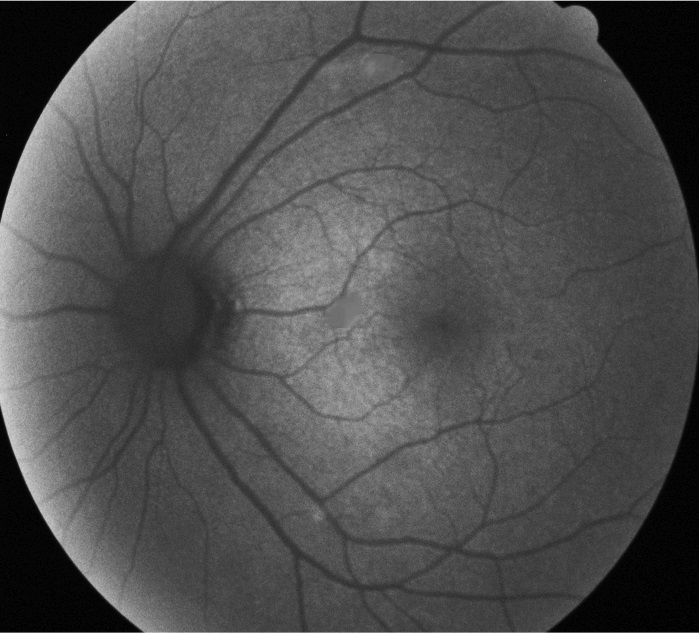

4.4 DCGANs and WGANs

In this section, DCGANs and WGANs are trained with thousands of CFP and FA images that have symptoms of drusen and GA separately; both of the models require four to six hours to train. Generated images have been diagnosed by ophthalmologists for verification. Images generated by DCGANs, which are shown in Fig. 8, cannot be identified as a valid retinal image with symptom. However, drusen and GA images generated by WGANs can be used by ophthalmologists to diagnose. In Fig. 9, generated drusen images are diagnosed as insignificant of drusen but can be identified by EyeNet. As for generated GA images in Fig. 9, irregularly shaped macular atrophy can be identified by an ophthalmologist. Macular atrophy is a distinguishable trait of GA, which means WGANs indeed learn the symptoms of drusen and GA from specific AMD and generate new images. Thus, WGANs perform better than DCGANs because of resolution. Structure of DCGANs limits the size of generated images to be 64x64, so some pathological details are lost. We choose WGANs for following experiments.

Figure 9: Drusen and GA images generated by WGANs.(a) Generated drusen CFP image. (b) Generated drusen FA image. (c) Generated drusen CFP image. (d) Generated GA FA image.

4.8 Neural Network Visualization for Retinal Images

Finally, we verified the hypothesis that vessel-based segmentation and contrast enhancement are two coherent features to decide the type of retinal diseases. Using techniques of generating CAMs introduced in [8], we visualized feature maps of the final convolutional layer of ResNet50 in Fig. 13. In our results, generated drusen images are well identified. However, generated GA images are not focused on the exact location of the symptom, but they are close. As discussed above, in the clinical diagnosis process, ”vessel patterns” and ”fundus structure” are the most crucial features for identifying the symptoms of different diseases. These types of features cover more than 80% of retinal diseases [27, 28].

Figure 13: Generated images and their CAMs. (a) Original drusen image (CFP). (b) Generated image of (a) by WGANs. (c) CAM of (b). (d) Original GA image (CFP). (e) Generated image of (d) by WGANs. (f) CAM of (e). (g) Original GA image (FA). (h) Generated image of (g) by style trnasferring. (i) CAM of (g).

We have implemented style transferring, DCGANs and WGANs to generate disease images that are detailed to capture different stages of AMD. Symptoms of images are drusen and GA; both FA and CFP images are generated. Images from DCGANs are difficult to be identified due to limit of resolution. However, images from style transferring and WGANs are easier to identify by ophthalmologists,and generated images preserve pathological details. EyeNet is used to predict the disease label, and results of generated drusen images are similar to original images. However, generated GA images are more distant compared to original images, because of the small number of GA images used during training EyeNet. This phenomenon shows that generated new images can be fed into the classifier to improve it. Also, CAMs are useful for extracting label-specific features. In Fig. 13(c),(f) and(i), warmer color parts are located in the well-demarcated areas or spots, which represents disease features that are close to those parts.